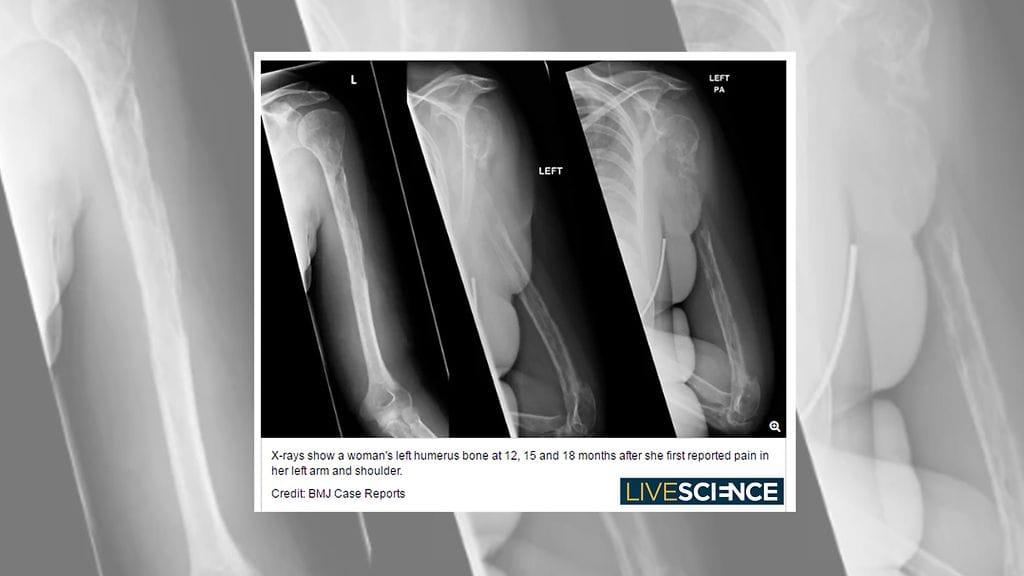

Nainen meni lääkäriin, koska käsivarsiin sattui – kärsikin äärimmäisen harvinaisesta taudista, jonka vuoksi hänen luunsa "katoavat"